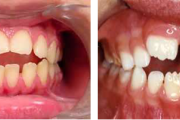

Lutipudelikaariese kahjustused

Lutipudelikaaries